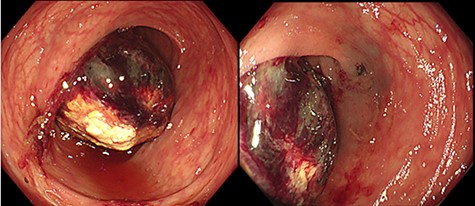

Her body height was 158.0 cm and her weight was 51.0 kg. Her abdomen was soft and without tenderness. There were no palpable tumors. Laboratory tests showed a white blood cell count of 5.3 × 109/L, a red blood cell count of 4.72 × 1012/L, and a hemoglobin level of 14.0 g/dl. Tumor markers such as carbohydrate antigen 19-9 and carcinoembryonic antigen were within normal levels. An abdominal enhanced computed tomography (CT) imaging performed on her first visit revealed a 3.5-cm low-density and low-enhanced tumor with intussusception in the left side of her colon. No swollen lymph nodes around the tumor were detected, and there was no evidence of any tumor invasion or metastasis (Fig. 2). We performed elective surgery for this patient because she had no alarming symptoms. Two weeks after her first visit, the patient was reexamined via abdominal CT scan. There were no findings of intussusception, and the same low-density tumor was found in her left transverse colon near the splenic flexure. Based on the above results, it is likely that the submucosal tumor of the left transverse colon caused intussusception.

Enhanced CT imaging of abdomen: (a) axial view. Three-layer like appearance indicating the intussusception was found in left side of colon (arrow). (b) Coronal view. The lead mass was detected as a 3.5-cm low-density tumor (arrowhead).